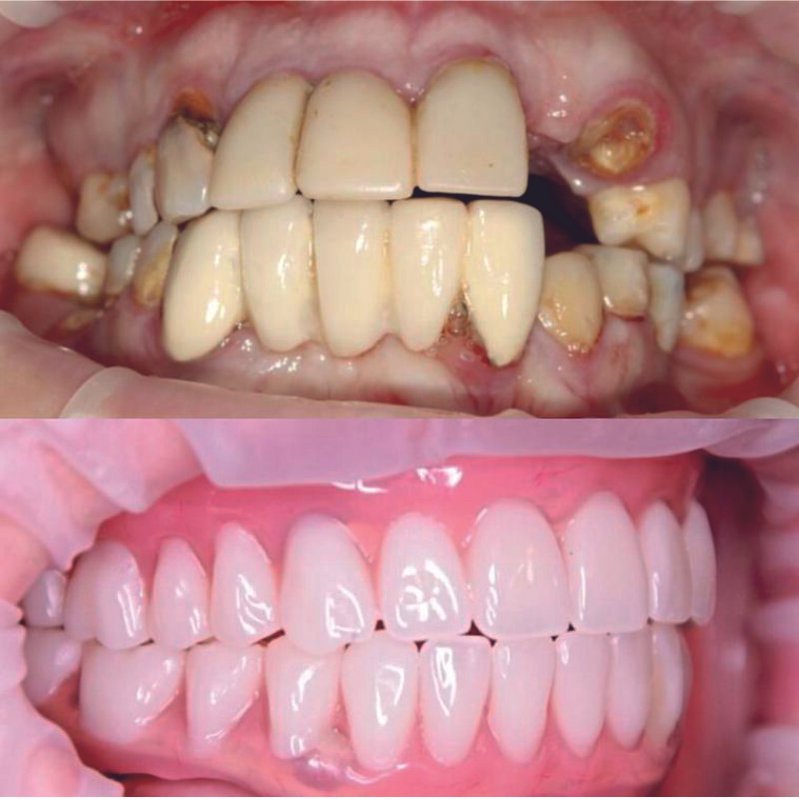

Фотогалерея